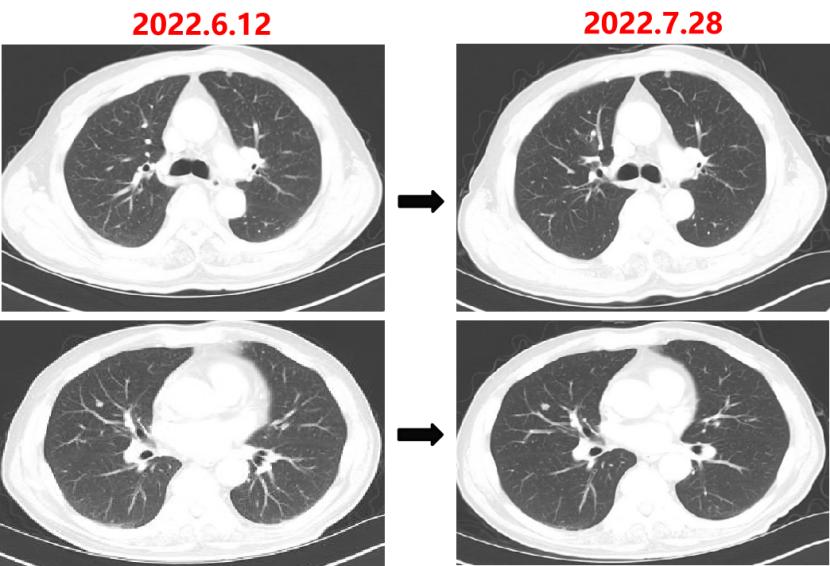

2022-06-12

肺无法穿刺活检。

基因检测示:(直肠)KRAS/BRAF/NRAS/PIK3CA 基因均未检出突变。伊立替康UGT1A1基因检测结果:非风险基因型。

CSCO指南:

2022-06-20:西妥昔单抗联合FOLFIRI方案治疗(西妥昔单抗900mg d1,伊立替康320mg d1,氟尿嘧啶0.7g iv 4.3g civ)。

2022-07-06:骨髓抑制、腹泻,西妥昔单抗联合FOLFIRI方案治疗(西妥昔单抗900mg d1,伊立替康280mg d1,氟尿嘧啶0.7g iv 4.3g civ)。

疗效对比: